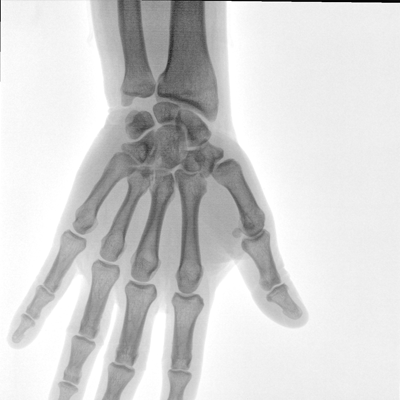

大尺寸液晶顯示器,圖像顯示清晰細膩;顯示器可大角度旋轉,滿足臨床多角度觀察圖像的需要。

在球管和平板探測器兩端,分別加裝了激光定位系統,滿足不同擺位無射線下的定位需求,降低醫患輻射劑量的同時,提高臨床工作效率。

濾線柵可插拔式設計符合行業標準,用于兒科和其他劑量敏感的臨床應用,使用簡便,保障圖像清晰的同時,可有效防護輻射危害。

DAP劑量顯示可以在使用機器的過程中,直接觀察到劑量顯示,保障醫患健康。